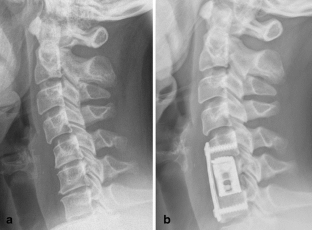

Fig. 3